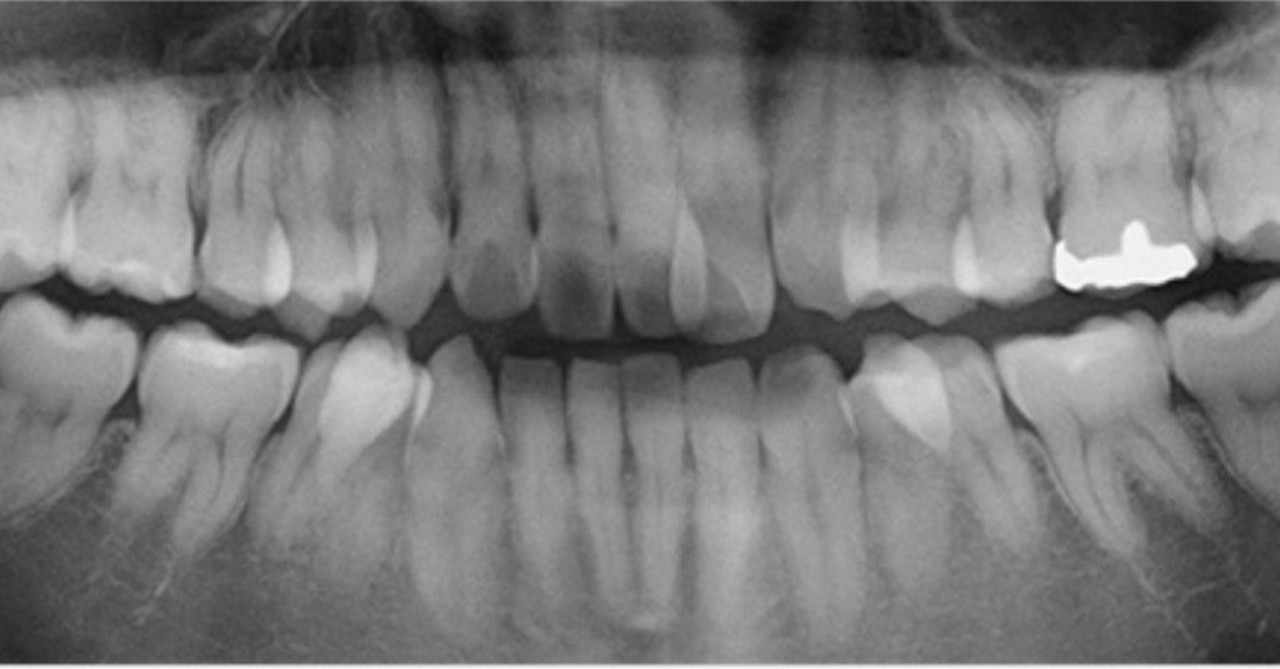

早わかり歯列矯正治療小児矯正 前編 矯正 香川県 香川矯正センター たくま歯科は世界水準の治療